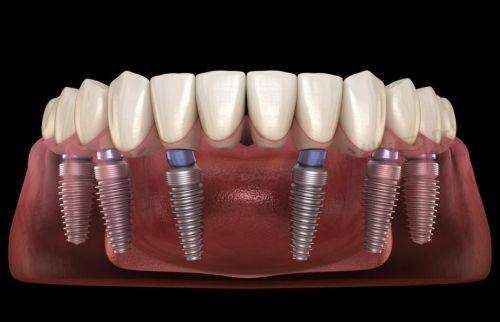

| 种植牙 | 2975元起 | 韩国仕诺康、奥齿泰、瑞士士卓曼等 | 含手术+种植体,不含牙冠 |